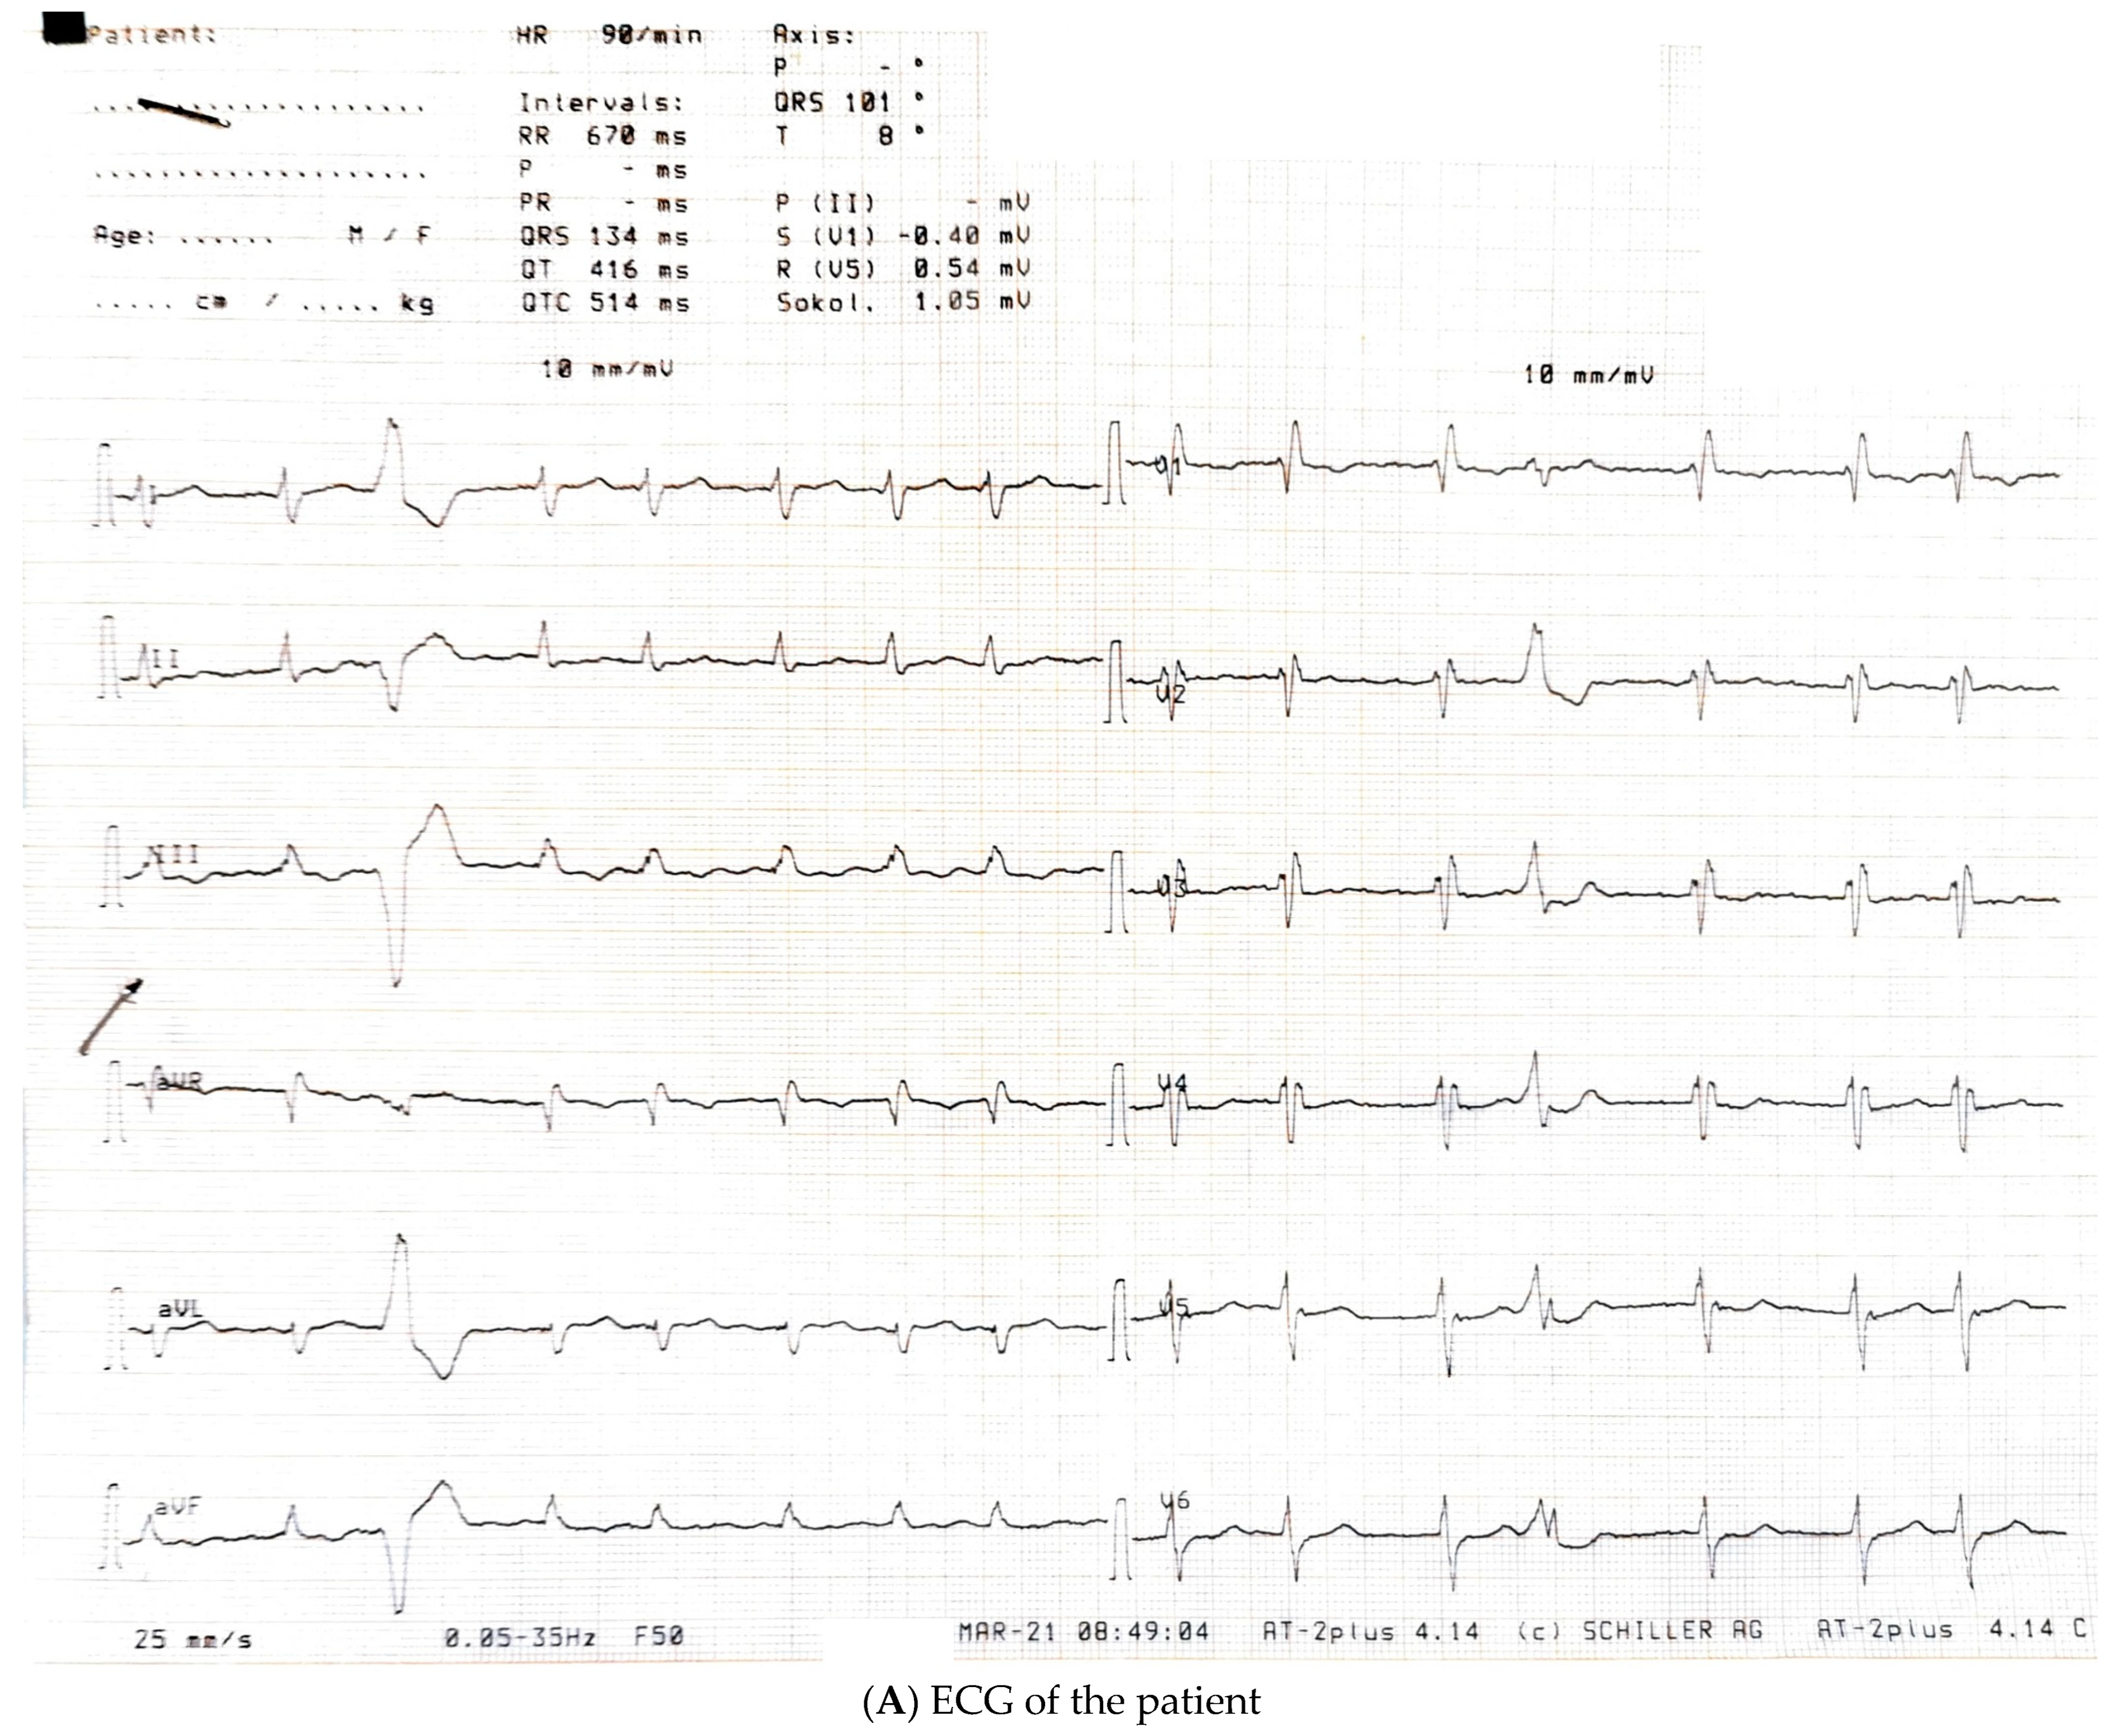

| March 2021, age 45 | First episode of decompensated heart failure, NYHA III-IV class; A new episode of persistent AF, duration longer than two months | Management of failure according to guidelines; TEE not performed due to INR not being in target; Asymmetric left ventricular hypertrophy and reduced ejection fraction noted; Further diagnostic work-up recommended—cardiac magnetic resonance (CMR) and genetic testing; Test for Anderson–Fabry disease—negative; CMR study positive for cardiomyopathy with diffuse fibrosis, possibly hypertrophic or infiltrative.  | At admission: Amiodarone 400 mg; Torasemide 20 mg; Irbesartan 75 mg; Acenocoumarol; At discharge: Torasemide 50 mg; Spironolactone 50 mg; Acenocoumarol; Bisoprolol 5 mg; Sacubitril/valsartan 2 × 24/26 mg; Allopurinol 150 mg; Dapagliflozin 10 mg  |